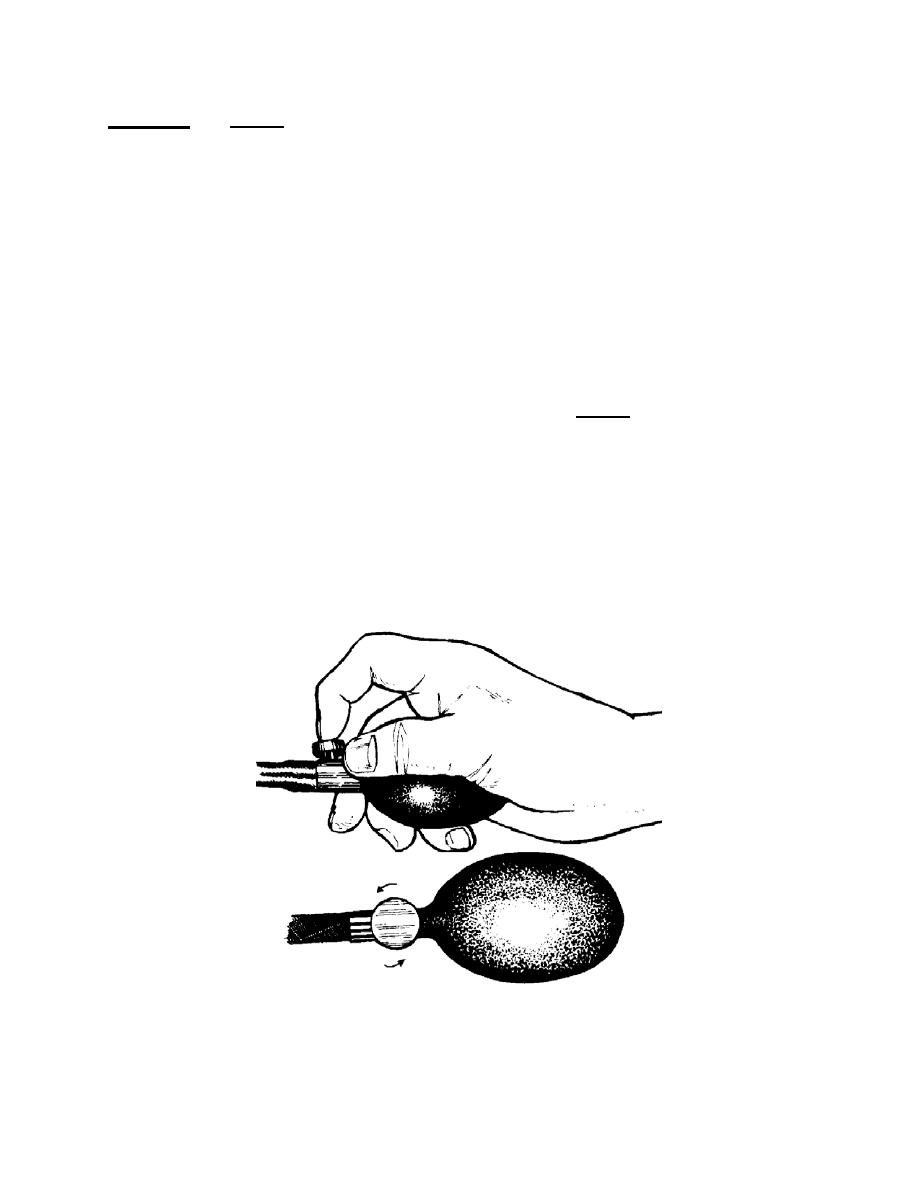

p. Release Air Slowly. Watch the gauge closely and listen through the

stethoscope as you release air from the bladder. Air is released from the bladder by

rotating the release valve (screw) counterclockwise (figure 5-10). The more the screw

is turned, the larger the opening and the faster the air escapes. You want the air to

escape slowly enough so that you can tell at what pressure reading the pulse

reappears, but fast enough that the continued pressure does not harm the patient or

cause unnecessary discomfort.

Figure 5-10. Rotating the screw counterclockwise to release pressure.